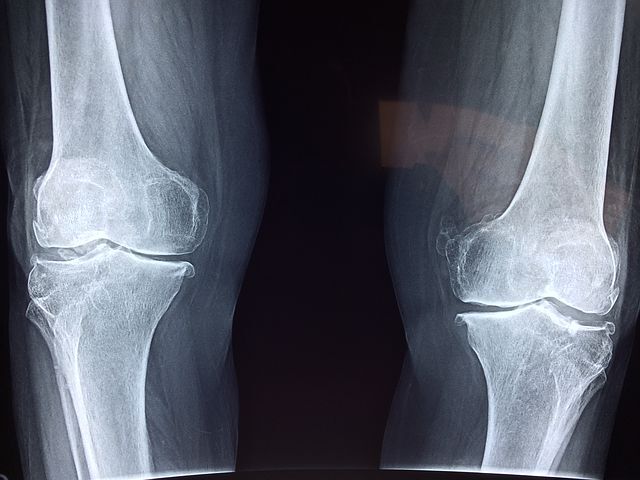

류마티스 관절염은 면역체계에 이상이 생겨 관절에 염증이나 부종등 심한 통증을 수반하게 되는데요. 연골과 뼈가 손상을입어 관절이 변형되고 관절의 기능이 저하되는 질환이라 할수 있습니다.

관절의 안쪽을 싸고있는 활막에 자주 염증이 쌓이게되면, 활막이 증가하고 주변 조직들을 파괴하는 것입니다. 전국에 대략 70 ~ 80 만명으로 추정되며, 특히 여성분들에게 많이 발병되고, 연령은 30 대 ~ 50 대가 피크라 할수 있습니다.

손이나 발가락 같은 작은 관절에 발병하는 경우가 많다고 볼수 있지만, 기간이 길어지면서 무릎이나 어깨ㆍ허리 등의 큰 관절에 염증이 전이되는 경우가 대부분입니다. 아직까지 왜 이런 증상들이 일어나는지 완벽하게 밝혀지지는 않았지만, 유전 적 요인과 흡연 습관, 잇몸 질환과 관련이 있다고 보고되고 있습니다.

류마티스 관절염 증상 초기에는 좌우 대칭으로 손가락과 발가락의 관절이 붓고, 아침에 경직을 느끼게 일반적이라 할수 있습니다. 시간이 흐름에따라 관절이 파괴되면, 작은 관절도 생활에 큰 불편함을 초래하게 되는 것입니다.

또한 환자는 무릎 관절이나 엉덩이 등 하체의 큰 관절에까지 영향을 미칠수있고, 걸음이 현저하게 곤란해질 수 있습니다.